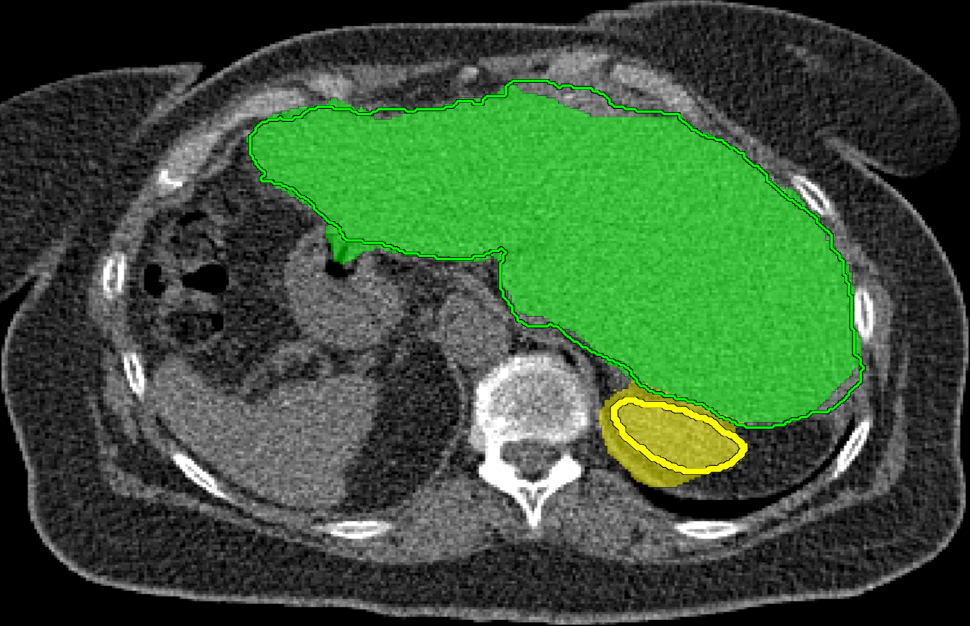

We applied our method on PET-CT scans of three different subjects to segment their liver, left kidney, right kidney and the background. Although we applied our method and Potts model on the 3D volumes we only show the results on a few representative slices from each volume in Fig.11. Also, the results of different methods for each subject were computed using the same smoothness. We can see from the last two rows which compare our method to Potts, using Hedgehogs constraints enabled us to avoid geometrically incorrect segmentations, e.g. one liver inside the other (last-row middle), or parts of left kidney is between the right kidney and liver (last-row right). Furthermore, for test subjects 1 and 2 the kidneys and background were poorly segmented by Potts model, e.g. most of the kidneys were segmented as background for test subject 1. Potts poor performance is due to the large overlap between the kidneys and background color models. This overlap resulted in an in-discriminative data term for Potts to properly separate them. This issue becomes worse in iterative frameworks where color models are re-estimated based on current segmentation. To be specific, if at any iteration Potts model resulted in a bad segmentation then re-estimating the color models will bias them towards the bad segmentation and subsequent iterations worsen the results. Comparing our results for subjects 1 and 2 to Potts model shows that our method is less prone to the aforementioned issue as we forbid undesirable segmentations, i.e. those that do not respect shape constraints.

| Subject 1 | Subject 2 | Subject 3 | |||

| Our method (Hedgehogs Shapes + Potts) | ![]() |

| \rdelim}1910pt Same Slice | |||||

|

Potts |

For quantitative comparison, Table 1 lists for each organ of a subject the Score, Precession and Recall measures of our method and Potts model where For the kidneys, our method clearly out performed Potts model, e.g. note Potts model poor precision/recall for subjects 1 and 2. For the liver, both methods performed comparably.